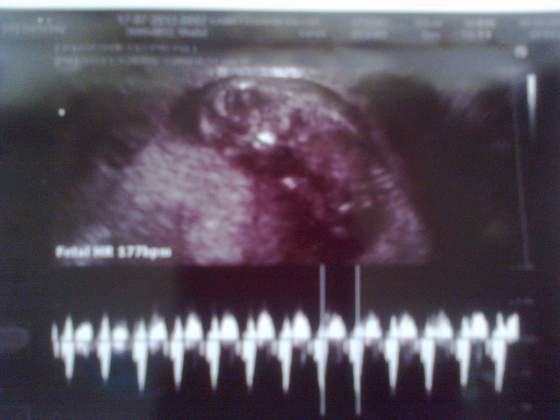

nasz Bąbel :) niecałe 3mm, 'serducho' pika jak szalone.

Nasze Maleństwo mialo 5mm 10sierpnia, a 20go na pewno zobaczymy serduszko mmmmm Tak bardzo Cie Kochamy mmuuuaaa :***** :)))))))))))